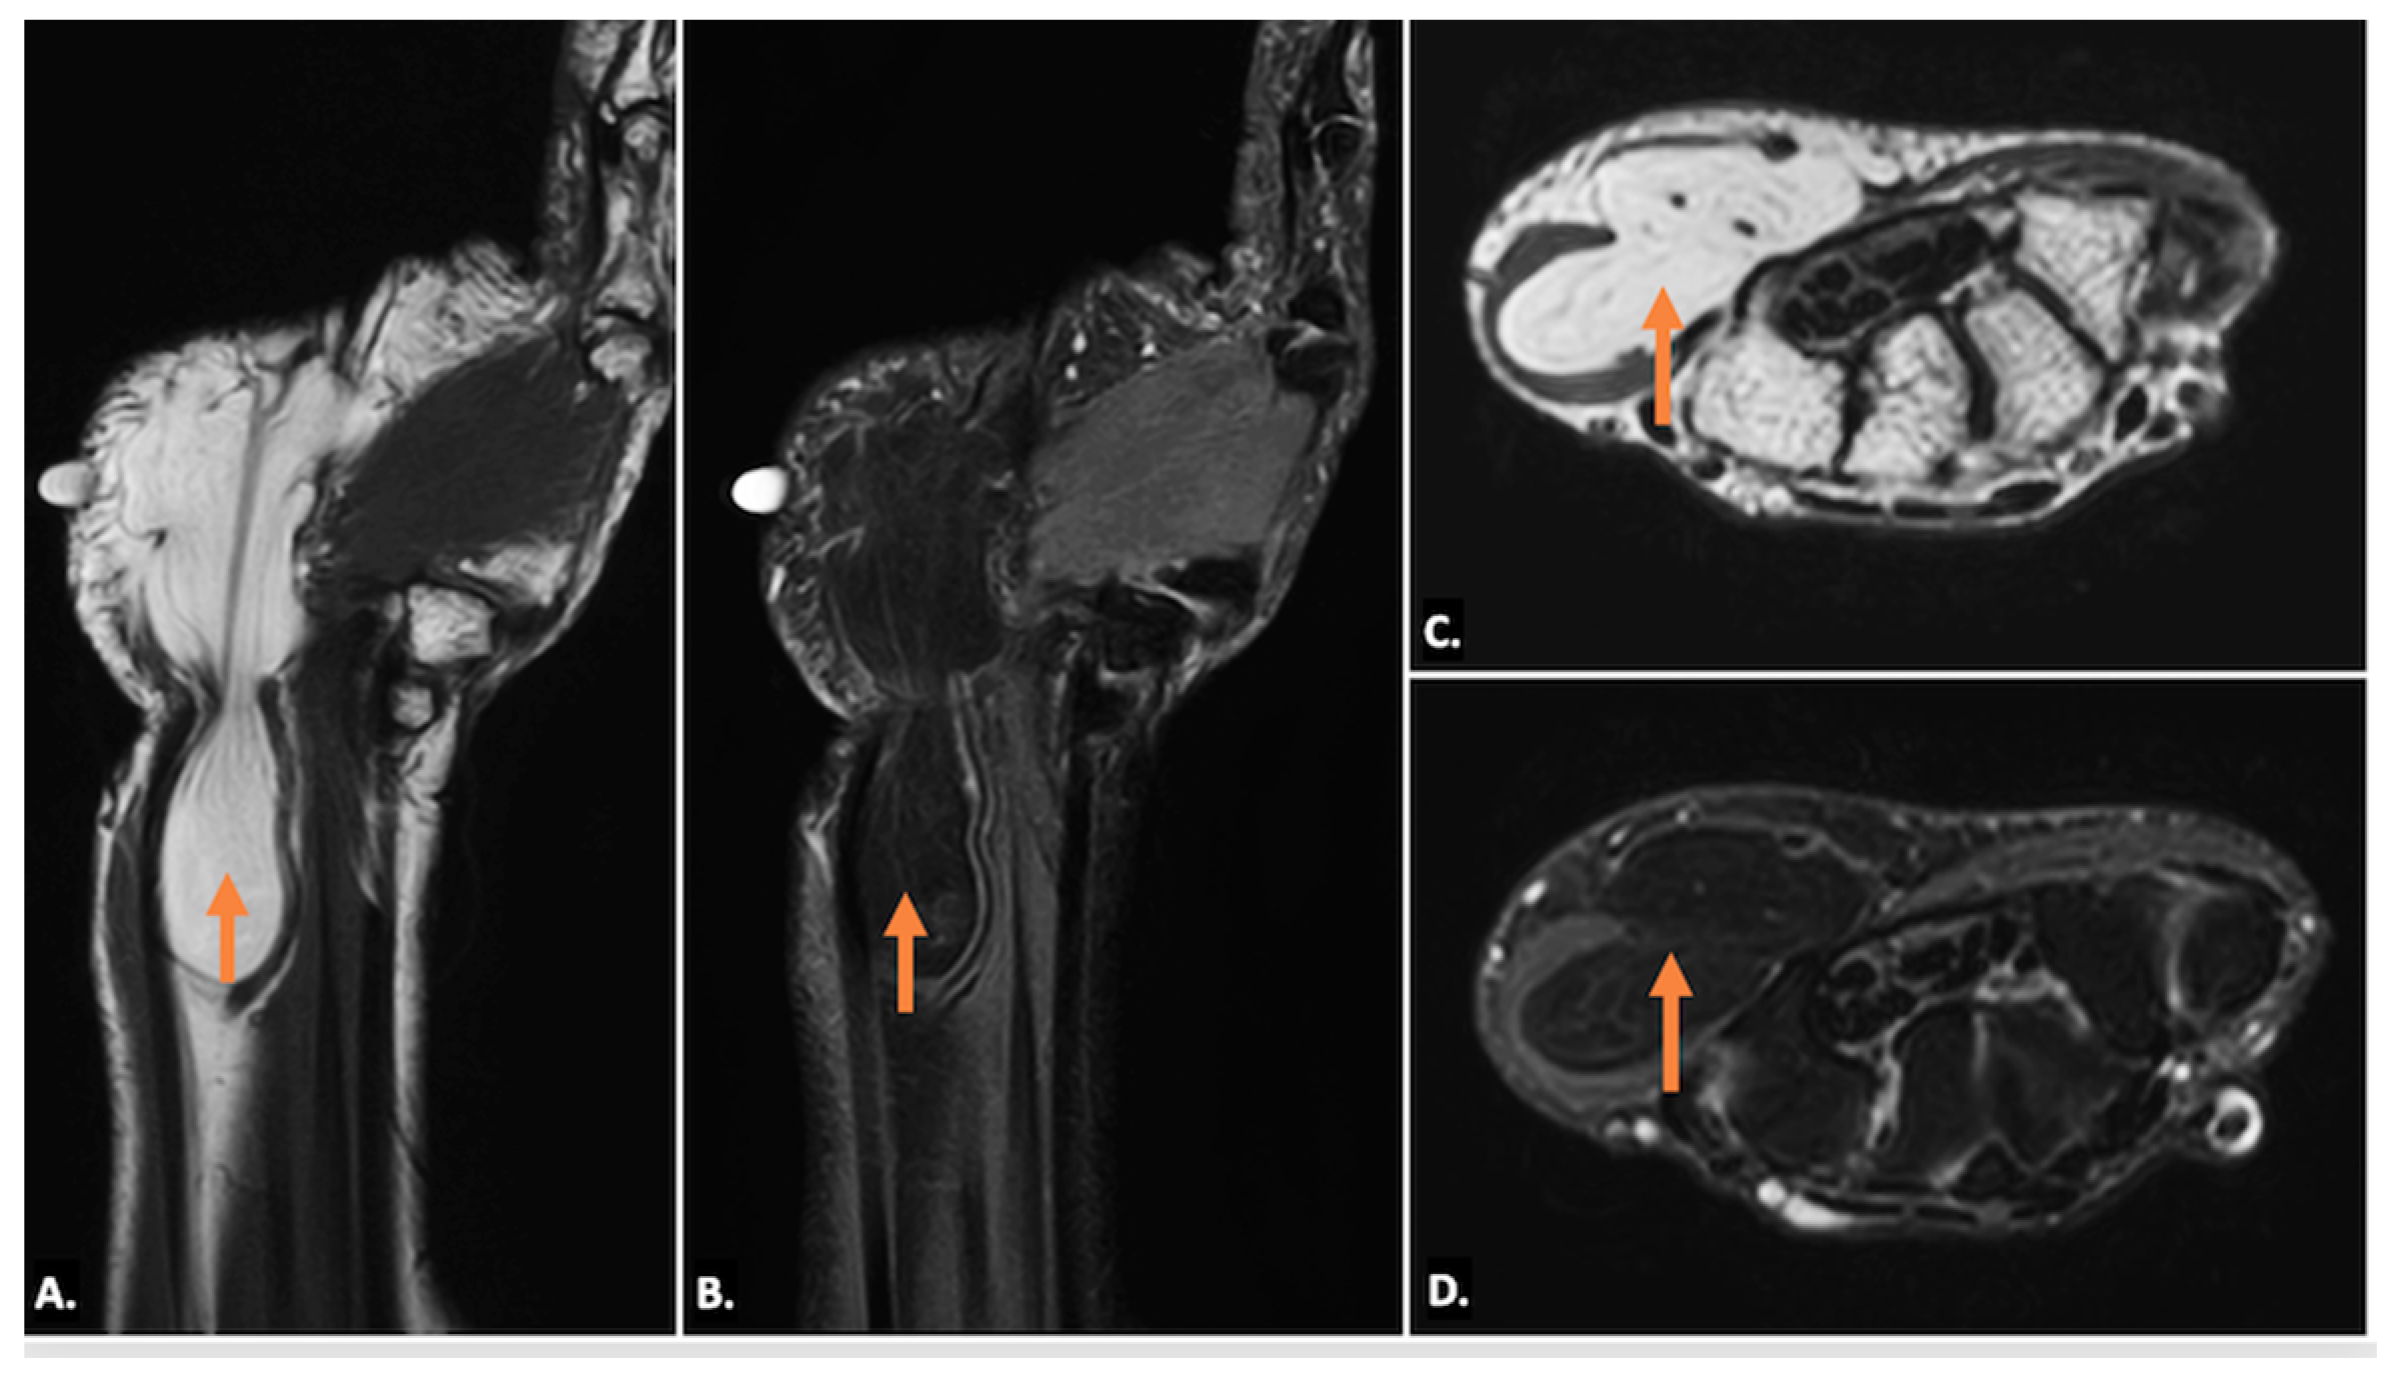

4.3. Ganglion Cysts

| Ganglion Cysts | A well-circumscribed anechoic or hypoechoic lesion with posterior acoustic enhancement. May show communication with joints or tendon sheaths. No internal vascularity on Doppler. | Well-defined, hypointense on T1 and hyperintense on T2-weighted images. Thin peripheral enhancement post-contrast. Possible nerve displacement/compression with T2 hyperintensity indicating oedema. |